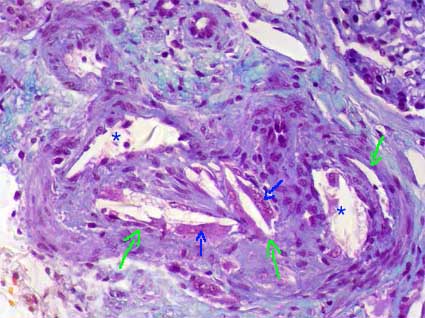

The distinctive and necessary finding for diagnosis is the presence of empty needle spaces in the lumen of arterioles, small arteries and occasionally arcuate arteries; these spaces are surrounded by fibrin thrombi and, if they have several days or weeks after they occurred, multinucleated giant cells (Figure 12). The spaces correspond to cholesterol crystals that dissolve with the normal processing of the tissue. To see these crystals is necessary to cut fresh frozen tissue and to see it with polarized light. Small emboli may reach glomerular capillaries and cause a gigantocellular reaction. In the first hours after the embolism there is infiltration of polymorphs that is after gradually replaced by lymphocytes and histiocytes. Depending on the involved artery we can see variable size infarcts. Surrounding ancient emboli a fibrous reaction develops.

Figure 12. This intrarenal artery is distortion due to cholesterol crystals in its lumen. These crystals disappear with the processing and remain the space they occupied as needles with pointed ends (elongated diamond) (green arrows). They are surrounded by inflammatory cells, mainly multinucleated giant histiocytes (blue arrows), and partially or completely obstruct the lumen. Asterisks indicate residual lumen of the artery. (Masson's trichrome, X300).